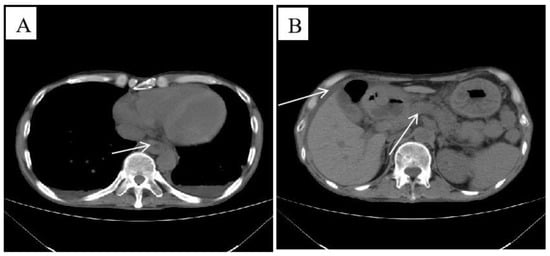

2. Case Presentation